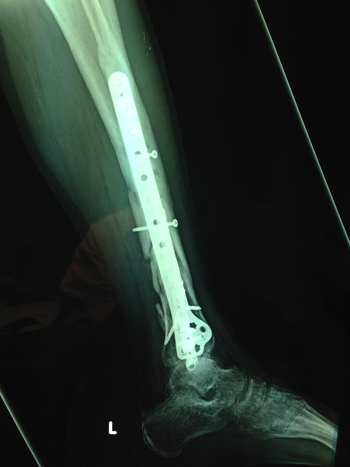

| Συντριπτικό κάταγμα κνήμης περόνης | Συντριπτικό κάταγμα κνήμης περόνης |